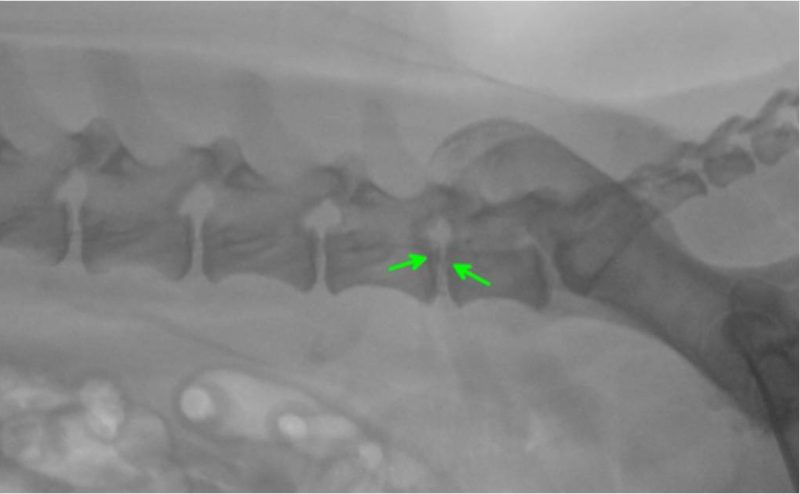

Die vor der Narkose durchgeführte Blutuntersuchung ergab keine Abweichungen von den Normalwerten. Die Röntgenbilder der Knie- und Hüftgelenke waren unauffällig. Bei der seitlichen Aufnahme der Lendenwirbelsäule fiel ein verengter und unruhiger Zwischenwirbelspalt zwischen dem 6. und 7. Lendenwirbel auf (Bild 1). Es wurde der Verdacht auf eine Bandscheibenerkrankung in diesem Bereich geäußert und den Besitzern eine weitere Abklärung mittels Computertomographie empfohlen. In der computertomographischen Untersuchung der Wirbelsäule konnte zwischen dem 6. und 7. Lendenwirbel in den knöchernen Wirbelkanal sowie in das linke Nervenaustrittsloch vorgefallenes Bandscheibenmaterial nachgewiesen werden (Bild 2 und 3). Dieses verursachte eine Kompression des Nervengewebes. Dieser Druck des vorgefallenen Bandscheibenmaterials auf das Nervengewebe war ursächlich für die hochgradige Schmerzhaftigkeit.